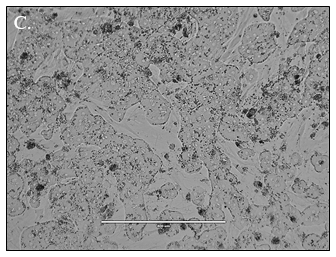

Predicting human hepatic clearance (CLhepatic) is often challenging in early drug development, particularly when low-clearance compounds are involved. To assess the metabolic stability of such drugs, suspended primary human hepatocytes (PHH) are commonly used; however, their ability to accurately predict in vivo CL, particularly of slowly cleared drugs, can be limited by short incubation times and rapid loss of enzymatic activity. To mitigate these issues, long-term in vitro models, like the Triculture System (TCS) developed by LifeNet Health, have been implemented in an effort to improve the characterization of hepatic metabolism and clearance in vitro by lengthening the amount of time hepatocytes can be cultured successfully. The TCS is an all-human cell-based in vitro model comprised of PHH and two different types of primary feeder cells (FC) that are plated together, shown in (Figure 1), on either a 24-well or 96-well collagen-I coated plate. In this study, the TCS (in both 24- and 96-well formats) was assessed for its functionality and its ability to predict human CLhepatic over the course of a 7- day incubation with no media change.

Hepatocytes in both the 24-well and 96-well formats appeared healthy morphologically and functionally demonstrated high levels of albumin secretion and relatively low levels of LDH release with no media change for up to 7 days when compared to values observed with daily media changes.